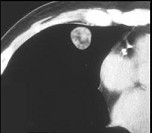

- 单项选择题女,71岁, 咳嗽,咳痰, 胸部隐痛2月余,请结合影像学检查, 选出最可能的诊断 ( )

A、肺癌

B、肺结核

C、肺错构瘤

D、结节病

E、肺转移瘤